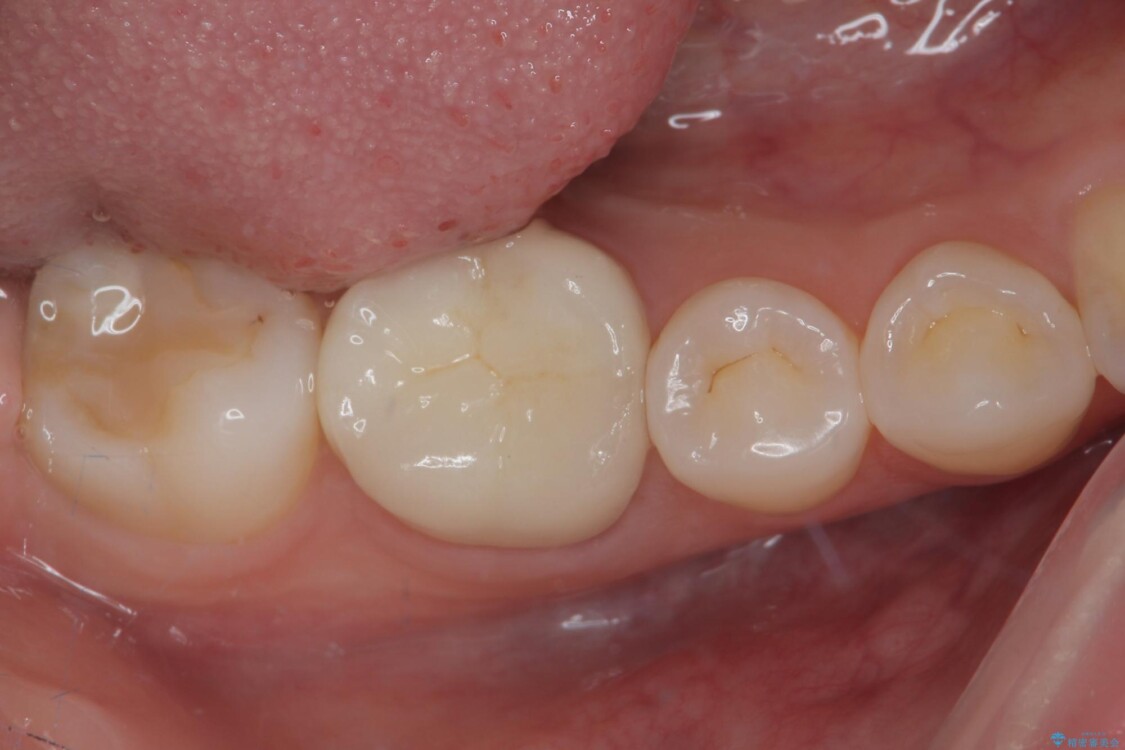

当院ではラバーダム防湿をし、根管内の感染源をしっかりと除去するために再根管治療を行いました。

その後、ファイバーコア(グラスファイバー製の支台)を築造し、最終的には精密な適合性と審美性に優れたオールセラミッククラウンによる補綴をしました。

このセラミッククラウンは、歯科技工士と連携し、1本1本の形・色・噛み合わせまで細部にこだわって製作しており、見た目の自然さだけでなく、長期的に安心して噛める機能性も重視しています。

• ラバーダム使用で再感染リスクを抑えた再根管治療+精密な補綴による長期安定を実現 治療後画像